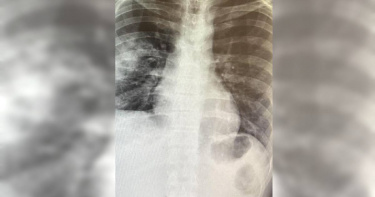

差點沒呼吸!年輕男流感入侵「併發肺塌陷」 醫警告:別忘這件事

由於疫情趨緩,不少民眾都逐漸脫下口罩,不過仍需注意的是,秋冬是呼吸道疾病得好發期,除了新冠肺炎,流感及黴漿菌等感染也都會導致喉嚨不適。對此,整合醫學專科醫師姜冠宇發文分享案例,表示近日一名年輕、無病史的患者,因流感而併發「肺塌陷」,一度險些沒呼吸,姜冠宇也呼籲民眾,每年都要記得接種疫苗。姜冠宇醫師日前在臉書粉專發文,提醒民眾「不要小看流感」,他也分享近日遇到的案例,一名30至40歲、完全沒有病史的健康年輕人,因為流感入侵下呼吸道併發「肺塌陷」,導致右肺葉扁了無法張開,一度差點沒了呼吸,所幸該年輕人對於症狀自覺得早,經治療預計很快便可摘掉氧氣罩。對此,姜冠宇醫師呼籲,平時要記得接種疫苗,「避免下呼吸道入侵這樣特殊的案例,讓所有的呼吸道病原體都盡量侷限在上呼吸道,免除危險症狀」,姜冠宇醫師指出,有時重症與本身體質有關,像是脆弱族群、孩童及年長者等,這些危險因子的推估不能代表一切,因此接種疫苗相當重要。一名年輕、無病史的患者,因流感而併發「肺塌陷」,一度險些沒呼吸。(圖/翻攝姜冠宇醫師臉書)